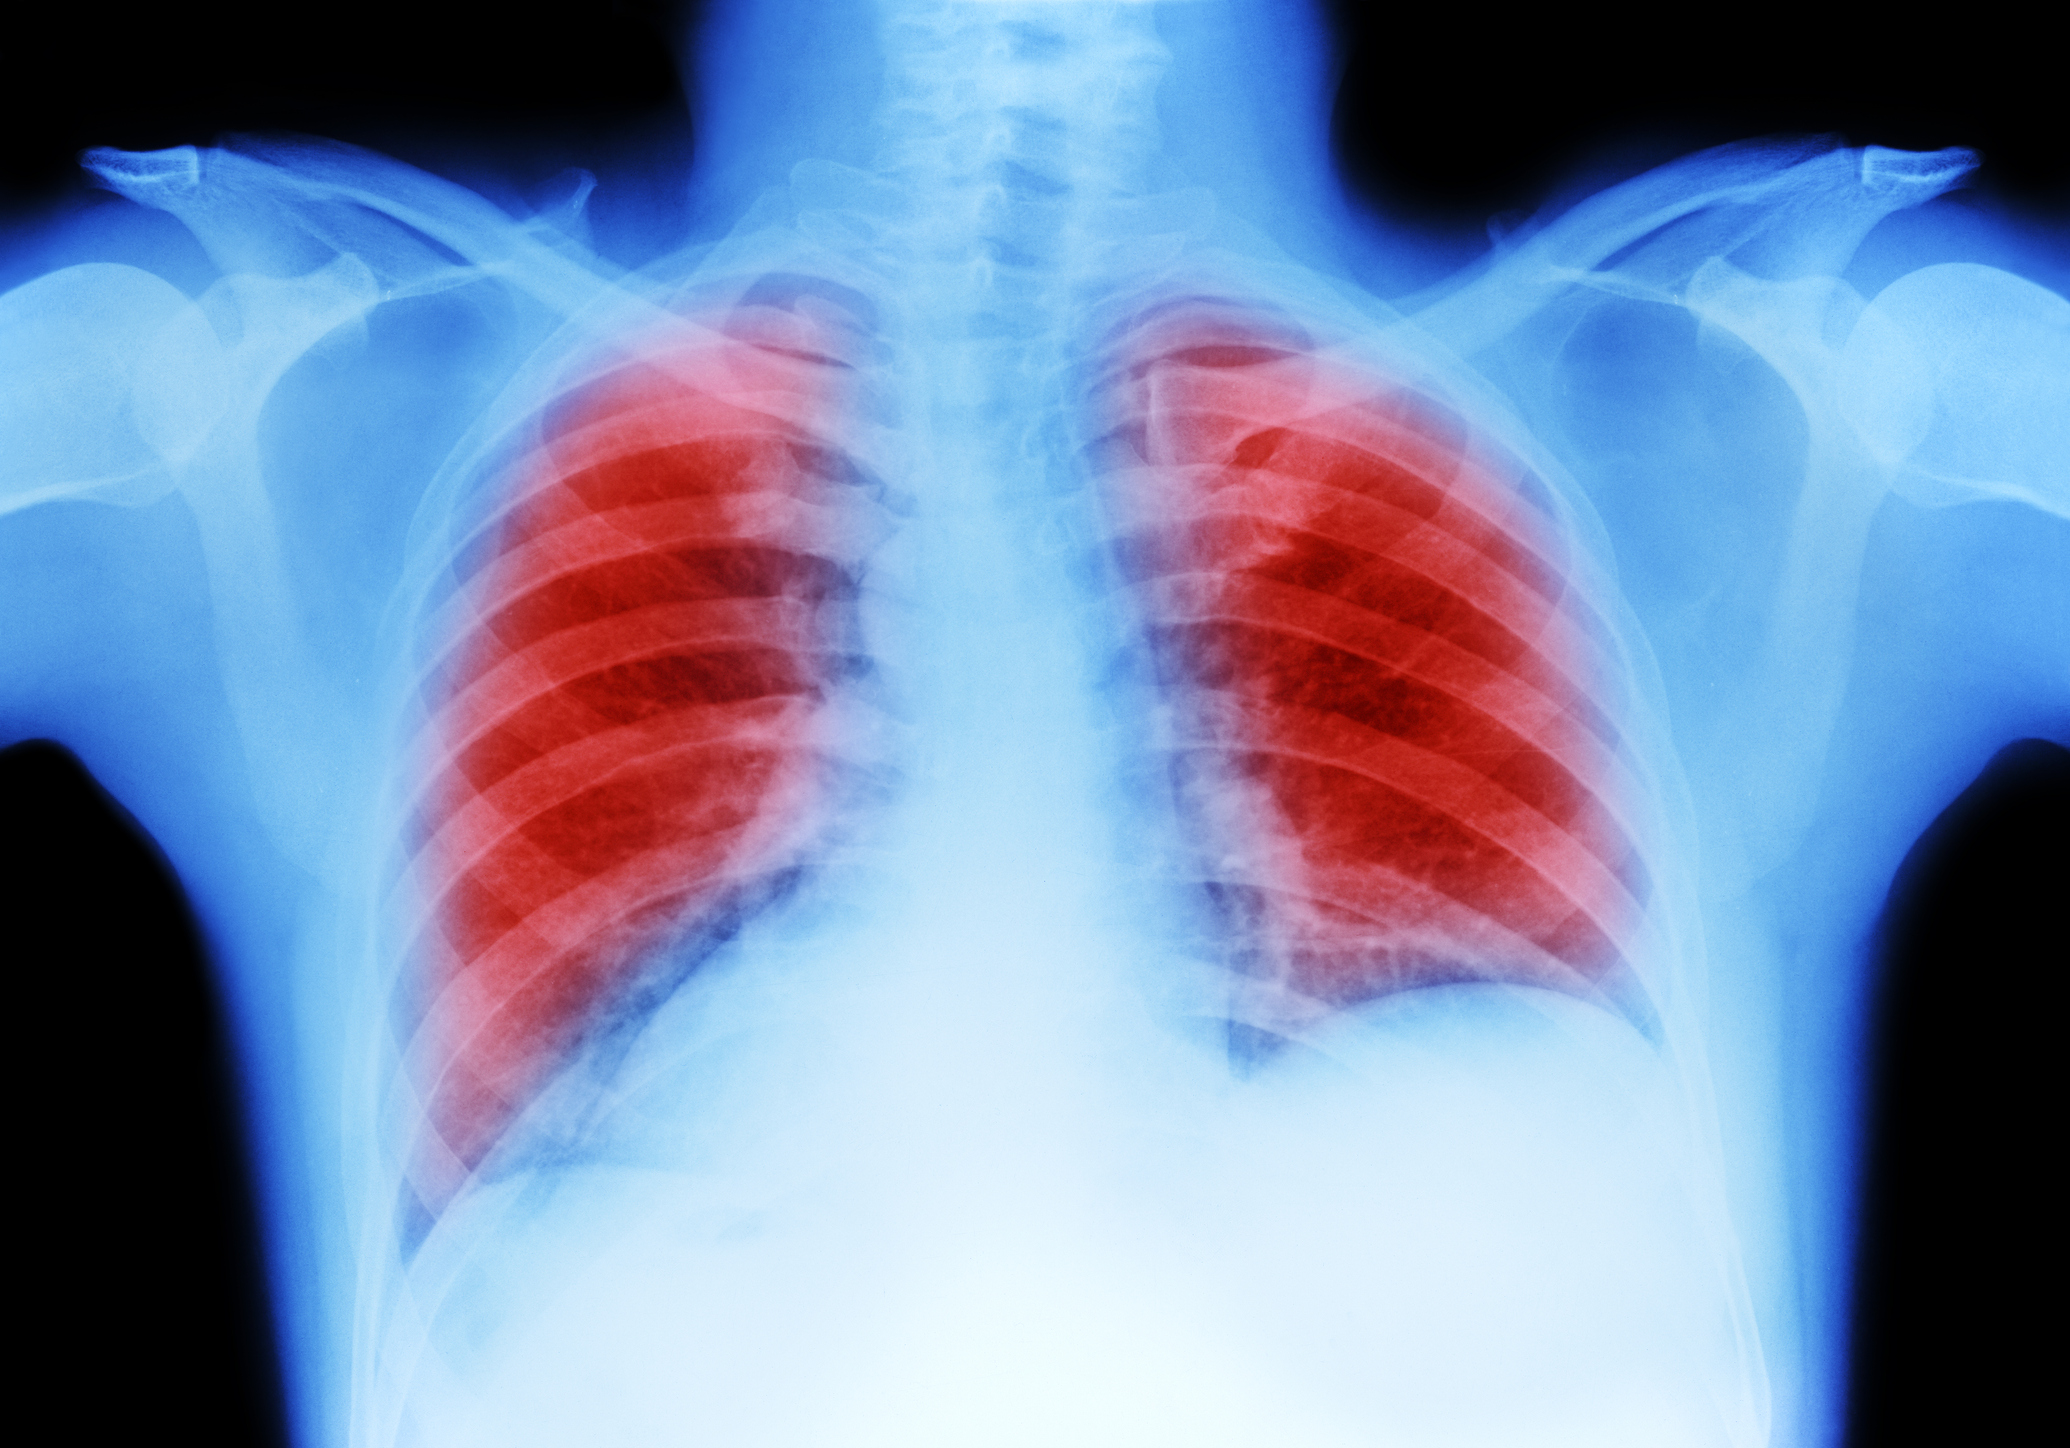

El de pulmón tiene una tasa de supervivencia a 5 años del 21%.

Como explica el medio citado anteriormente, un informe encargado recientemente por el Ministerio de Sanidad al Servicio Canario de Salud y a la Agencia Gallega para la Gestión del Conocimiento de Salud ha determinado que el cribado del cáncer de pulmón no saldría rentable. Los expertos que han analizado este tema consideran que reduciría "ligeramente" el riesgo de muerte, pero no aprecian beneficios globales en su aplicación a más parte de la población.